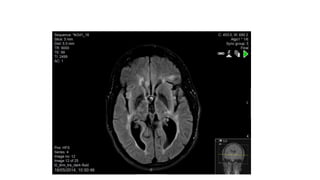

Infratentorial Lesions

31 March 2014 Gadolinium enhancement of symptomatic lesion